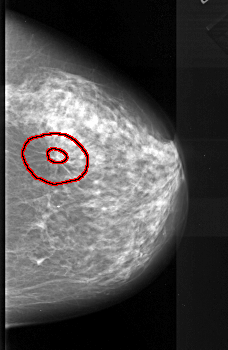

A_1087_1.RIGHT_CC

RIGHT_CC LINES 5596 PIXELS_PER_LINE 3646 BITS_PER_PIXEL 16 RESOLUTION 42 OVERLAY

FILE: A_1087_1.RIGHT_CC.OVERLAY

TOTAL_ABNORMALITIES 1

ABNORMALITY 1

LESION_TYPE MASS SHAPE ARCHITECTURAL_DISTORTION MARGINS SPICULATED

ASSESSMENT 5

SUBTLETY 1

PATHOLOGY MALIGNANT

TOTAL_OUTLINES 2

BOUNDARY

CORE